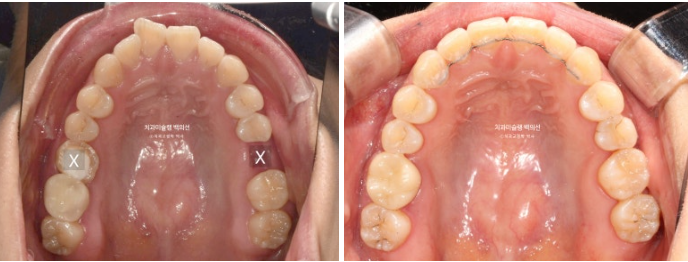

상악은 빼야하는 제 1대구치 (첫번째 큰어금니) 두 개를 빼고 공간을 없애면서 앞니를 뒤로 보내고 사랑니 큰어금니 자리로 데려와 대체하여 쓰기로 합니다.

이렇게 하면 큰어금니 자리를 임플란트 없이 교정으로 마무리가 가능하니 일석이조 입니다

하악은 양쪽 사랑니를 빼고 사랑니 공간으로 후방이동 시켜 앞니를 뒤로 보내기로 합니다.

발치된 큰어금니 자리를 뒤에있는 제2대구치와 사랑니로 감쪽같이 대체되었습니다.

23.10~25.08